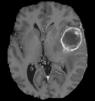

Machine learning has been widely adopted for medical image analysis in recent years given its promising performance in image segmentation and classification tasks. The success of machine learning, in particular supervised learning, depends on the availability of manually annotated datasets. For medical imaging applications, such annotated datasets are not easy to acquire, it takes a substantial amount of time and resource to curate an annotated medical image set. In this paper, we propose an efficient annotation framework for brain MR images that can suggest informative sample images for human experts to annotate. We evaluate the framework on two different brain image analysis tasks, namely brain tumour segmentation and whole brain segmentation. Experiments show that for brain tumour segmentation task on the BraTS 2019 dataset, training a segmentation model with only 7% suggestively annotated image samples can achieve a performance comparable to that of training on the full dataset. For whole brain segmentation on the MALC dataset, training with 42% suggestively annotated image samples can achieve a comparable performance to training on the full dataset. The proposed framework demonstrates a promising way to save manual annotation cost and improve data efficiency in medical imaging applications.

翻译:近年来,由于在图像分割和分类任务方面表现良好,医学图像分析广泛采用了机器学习。机器学习的成功,特别是监督学习的成功,取决于手动附加说明数据集的可用性。对于医疗成像应用来说,这种附加说明数据集不容易获得,需要大量的时间和资源来翻译附加说明的医学成像集。在本文件中,我们建议为大脑MR图像建立一个高效的注释框架,为人类专家提供信息性样图像,供人类专家作说明。我们评估了两种不同的大脑图像分析任务的框架,即脑肿瘤分割和整个大脑分割。实验显示,对于BRATS 2019数据集的脑肿瘤分割任务,培训一个只有7%的附加说明图像样本的分解模型,其性能与全数据集培训的性能相当。对于MALC数据集的整个大脑分割,用42%的附加说明性图像样本进行的培训,可以实现与全数据集培训的类似性能。拟议的框架展示了节省人工注解成本和提高医疗成像应用数据效率的有希望的方法。